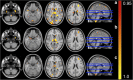

NeAT is a modular, flexible and user-friendly neuroimaging analysis toolbox for modeling linear and nonlinear effects overcoming the limitations of the standard neuroimaging methods which are solely based on linear models. NeAT provides a wide range of statistical and machine learning non-linear methods for model estimation, several metrics based on curve fitting and complexity for model inference and a graphical user interface (GUI) for visualization of results. We illustrate its usefulness on two study cases where non-linear effects have been previously established. Firstly, we study the nonlinear effects of Alzheimer's disease on brain morphology (volume and cortical thickness). Secondly, we analyze the effect of the apolipoprotein APOE-ε4 genotype on brain aging and its interaction with age. NeAT is fully documented and publicly distributed at https://imatge-upc.github.io/neat-tool/ .